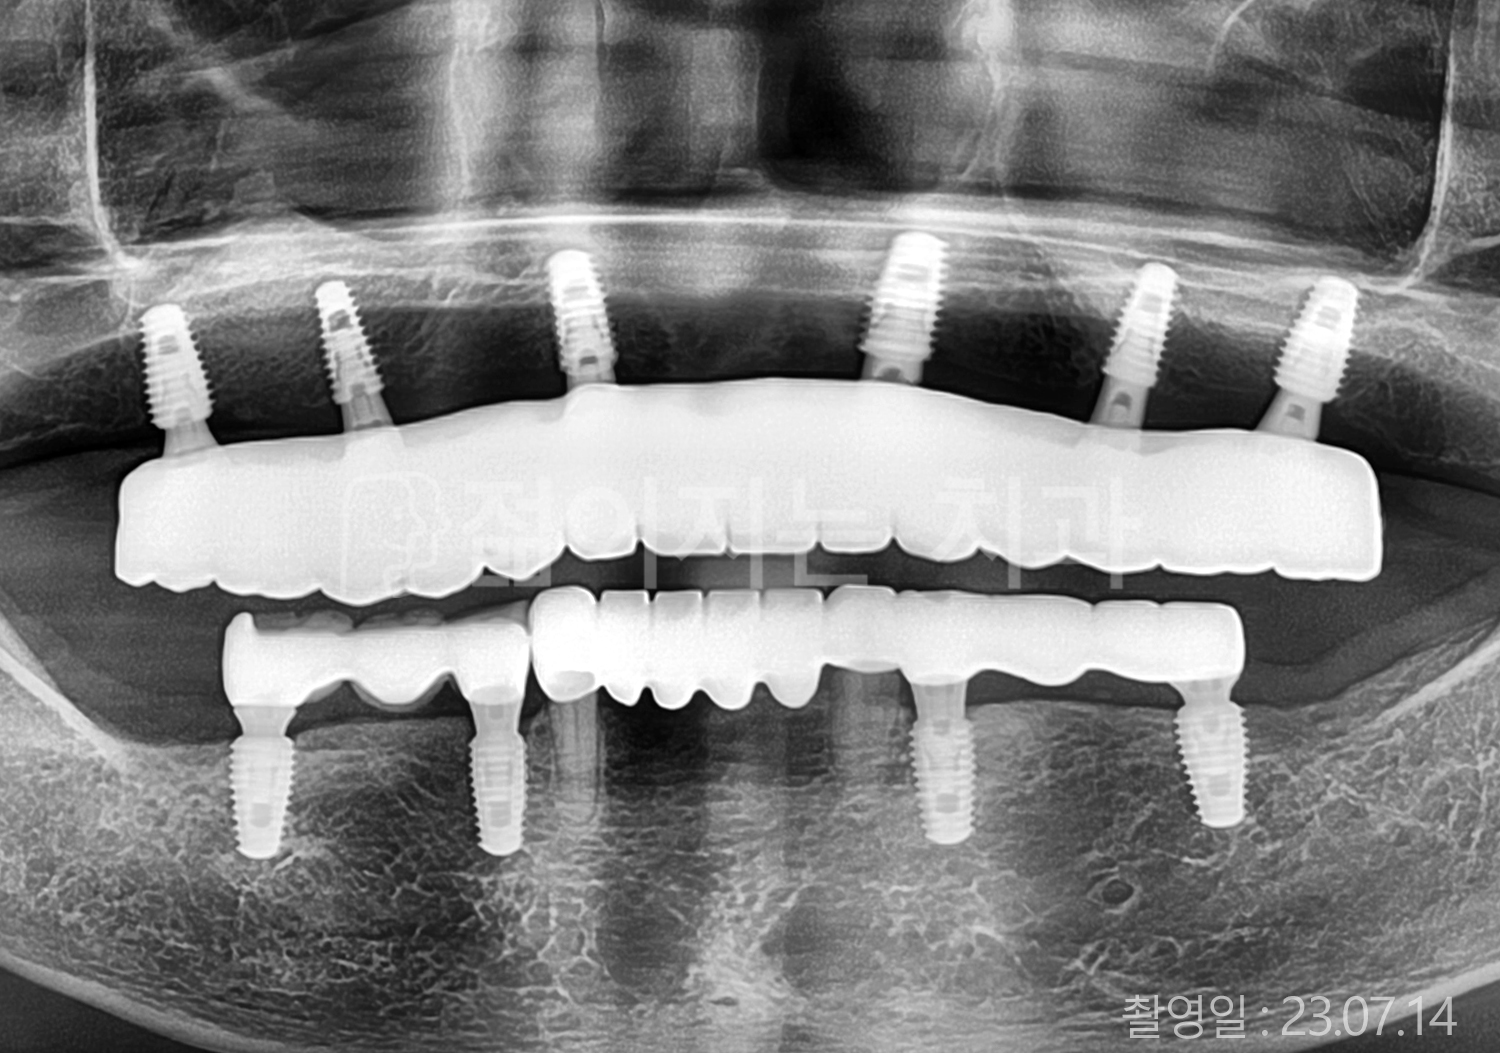

• 50대 고혈압, 고지혈증 전체치아 10개 이상 임플란트